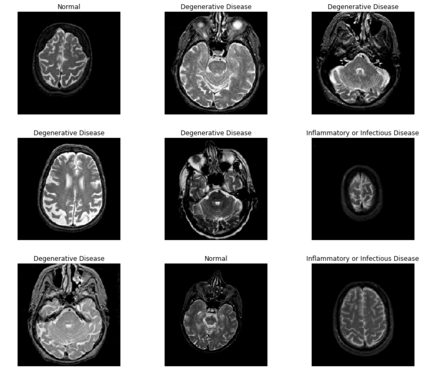

Magnetic Resonance Imaging (MRI) is a principal diagnostic approach used in the field of radiology to create images of the anatomical and physiological structure of patients. MRI is the prevalent medical imaging practice to find abnormalities in soft tissues. Traditionally they are analyzed by a radiologist to detect abnormalities in soft tissues, especially the brain. The process of interpreting a massive volume of patient's MRI is laborious. Hence, the use of Machine Learning methodologies can aid in detecting abnormalities in soft tissues with considerable accuracy. In this research, we have curated a novel dataset and developed a framework that uses Deep Transfer Learning to perform a multi-classification of tumors in the brain MRI images. In this paper, we adopted the Deep Residual Convolutional Neural Network (ResNet50) architecture for the experiments along with discriminative learning techniques to train the model. Using the novel dataset and two publicly available MRI brain datasets, this proposed approach attained a classification accuracy of 86.40% on the curated dataset, 93.80% on the Harvard Whole Brain Atlas dataset, and 97.05% accuracy on the School of Biomedical Engineering dataset. Results of our experiments significantly demonstrate our proposed framework for transfer learning is a potential and effective method for brain tumor multi-classification tasks.